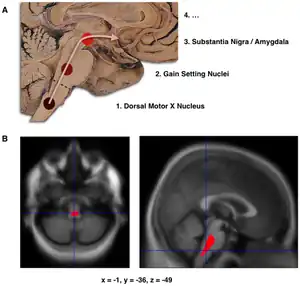

B. Localization of the area of significant brain volume reduction in initial PD compared with a group of participants without the disease in a neuroimaging study which concluded that brain stem damage may be the first identifiable stage of PD neuropathology.[1]

The disease begins in structures of the lower brainstem and the olfactory system. In particular, the dorsal motor nucleus of the vagus nerve in the medulla oblongata and anterior olfactory nucleus are affected.[6] Lewy neurites, thread-like alpha-synuclein aggregates, are more prevalent than globular Lewy bodies in this stage.[4]